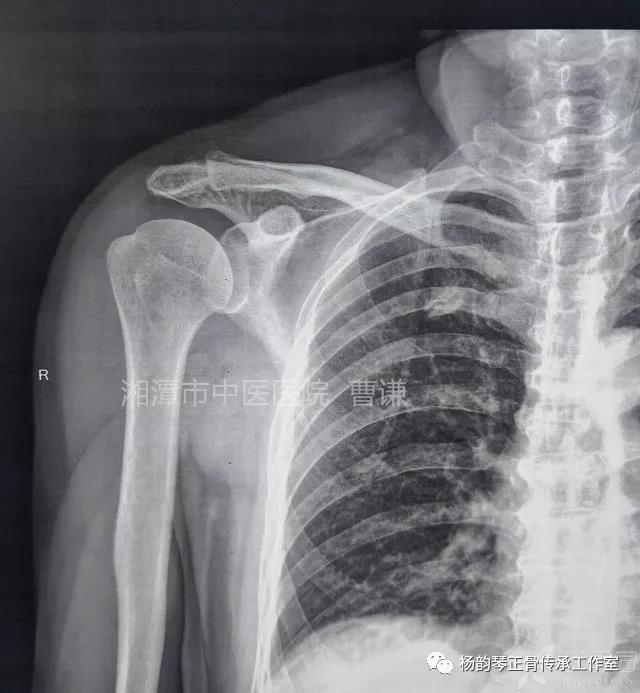

就诊我院后完善CT,诊断明确——左肩关节后脱位:

予以手法复位后拍片复查显示“灯泡征”消失,复位成功。讨论:肩关节后脱位在临床较为少见,特别是影像科经验不足很容易漏报,所以我们临床医生一定要自己仔细阅片,同时要结合体查来进行诊断,防止漏诊。肩关节后脱位时体查也有明显特征:肩关节前方明显变平,喙突较平时明显凸起容易触及,而肩关节后方明显丰满,上臂一般处于内旋内收位,无法主动外旋外展。肩关节后脱位的手法复位相对于前脱位的复位来说也比较容易。患者一般可以取坐位,助手自患侧腋下环抱患者稳定患者躯体,术者一手拉患肢上臂稍牵引内旋,一手自后方推顶肱骨头一般可以复位,如果单纯推顶无法复位也可以术者两手握住伤肢缓慢外展并沿肱骨纵轴牵引,然后逐渐外旋上臂即可复位。整复完成后可以把持患肢作肩关节各个方向的小幅度被动活动,防止肩关节粘连,肩关节后脱位的固定方法与肩关节前脱位的固定方法不同,应将患肢置于上臂外展、后伸、外旋位固定,即外展30度、后伸30度和轻度外旋位,用外展支架固定3周后,循序渐进开始肩关节功能康复。